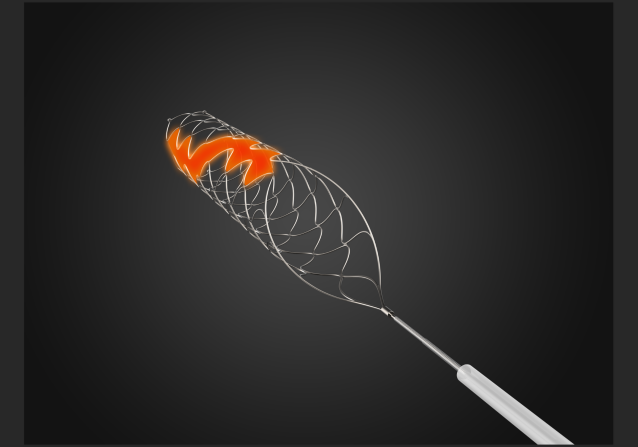

支架:蛟龙 4*30

支架规格齐全,本病例4*30支架,支架足够长,增加血栓夹持力,提高开通率。

该病例是心源性栓塞,血栓质韧,本例选用蛟龙4*30mm更长的取栓支架,更长长度提供更大表面积接触血栓,以独特的侧边螺旋开放结构,帮助快速高效一次三级再通。一篇研究回顾性分析了2011年6月到2017年3月使用直径4mm取栓支架及球囊指引导管作为首选治疗策略治疗ICA、MCA急性闭塞的病例。该研究中,4×30mm和 4×40mm被定义为长支架,4×20mm被定义为短支架。主要的临床结局是一次性取栓血管成功再通率(mTICI 2b/3)。研究共纳入420例患者,其中221例(53%)患者使用长支架,119例(47%)使用短支架。相对于短支架,长支架组一次性取栓血管开通率(62% vs 50%;P=0.01)和最终血管开通率(mTICI2b/3,98% vs 94%;P=0.01)更高。长支架一次性取栓成功开通率高的原因,可以从以下几方面来解释:长血栓会提供更大的表面积与取栓支架接触包裹血栓,也会在取栓过程中使张力均匀分布,在血管路径扭曲或者躁动的病人中,长支架通过增加可接受的误差范围来实现精确释放。更长的支架会增加取栓装置向血栓远端延伸的移动力,同时,在支架首个与血栓接触的网孔抓捕血栓失败的情况下,可以增加血栓取出的机会。[1]因此,通桥医疗即将上市的蛟龙4*30mm取栓支架在临床上的广泛应用值得期待。